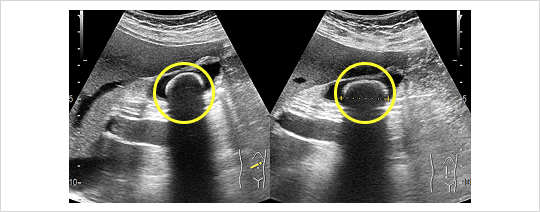

超音波検査

負担なく胆のうの状態や結石を直接みることができます。ただし食事後や肥満体型の方は診断が難しくなります。